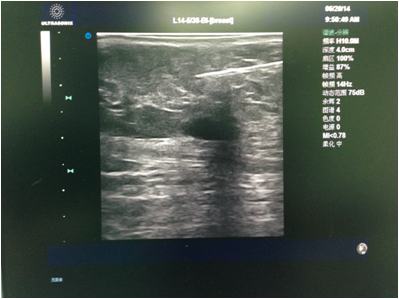

先由主刀医生行彩超检查,和患者确认及核对拟切除的目标病灶。消毒铺巾后医生在彩超引导下于表皮,手术路径及目标病灶周围注射局麻药(图1)。麻醉满意后于彩超引导下进旋切针到目标病灶下方,然后开始切除目标病灶(图2)。最后加压包扎,切除的病灶送病理检查(图3)。整个手术过程于局麻下完成,会有轻微疼痛,但一般程度不重。

图2 图中低回声为肿物,下方白色条索为旋切针。经过旋切后,可以看到肿物消失。